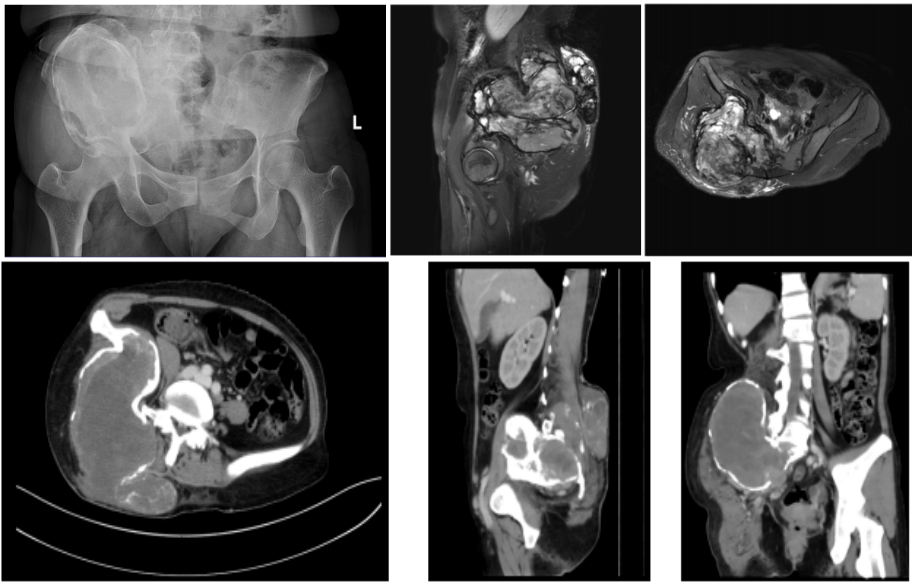

图1术前影像学检查。影像学提示骶骨及髂骨区巨大肿瘤,肿瘤对周围组织形成压迫并且造成骨盆垂直移位。

术前影像学检查。影像学提示骶骨及髂骨区巨大肿瘤,肿瘤对周围组织形成压迫并且造成骨盆垂直移位。

该患者为41岁女性,术前穿刺病理诊断为侵袭性骨巨细胞瘤。骨巨细胞瘤是一种常见的原发性骨肿瘤,好发于20-40岁青壮年,虽多为良性,但具有局部侵袭性,可破坏骨骼结构,压迫周围神经血管。患者肿瘤位于骨盆I/IV区——即骶骨与髂骨区域,此处解剖结构复杂,紧邻髂血管、骶神经及坐骨神经,肿瘤已对这些关键组织造成明显压迫及侵袭,导致患者出现右侧大腿及下肢放射痛、髋关节活动障碍等症状。